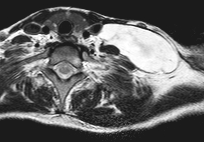

4. image: Young male patient with a left supraclavicular lump. Upper panel: complex cystic mass with sepatations; normal flow in the neighbouring vessels. Lower panel: T2W, postcontrast T1W, fat-saturation T1W MRI suggest cystic lymphangioma (Asklepios Klinik Altona, Hamburg)